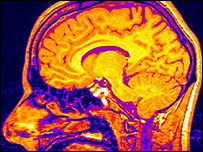

نکته حائز اهميت در اين تحقيق نحوه پردازش تصاوير در مغز است

مقاله ای که اکنون به قلم حسين استکی و دو پژوهشگر ديگر ايرانی، سيد رضا افراز و روزبه کيانی، در نيچر به چاپ رسيده حاصل پژوهشی مشترک در سه زمينه علوم اعصاب، رياضيات و فيزيک نظری است و نکته حائز اهميت در آن نحوه پردازش تصاوير در مغز است.